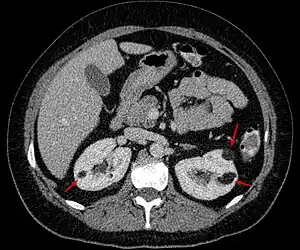

| Angiomyolipoma in both kidneys (arrows) as seen on CT scan. The tumors are hypodense (dark) due to fat content. | |

They occur in up to 90% of cases of tuberous sclerosis (TSC) and 50% of cases of lymphangioleiomyomatosis (LAM).[1][3] In tuberous sclerosis often multiple lesions are present.[3] They may also occur spontaneously.[3] They can usually be diagnosed by CT scan or MRI.[3]

Incidental discovery of angiomyolipomas should trigger consideration of tuberous sclerosis complex (TSC) and lymphangioleiomyomatosis, especially if they are large, bilateral, and/or multiple. Screening for TSC includes a detailed physical exam, including dermatologic and ophthalmologic evaluations, by TSC expert clinicians and a CT or MRI of the brain. Screening for LAM includes a high-resolution CT of the lung and pulmonary function testing.